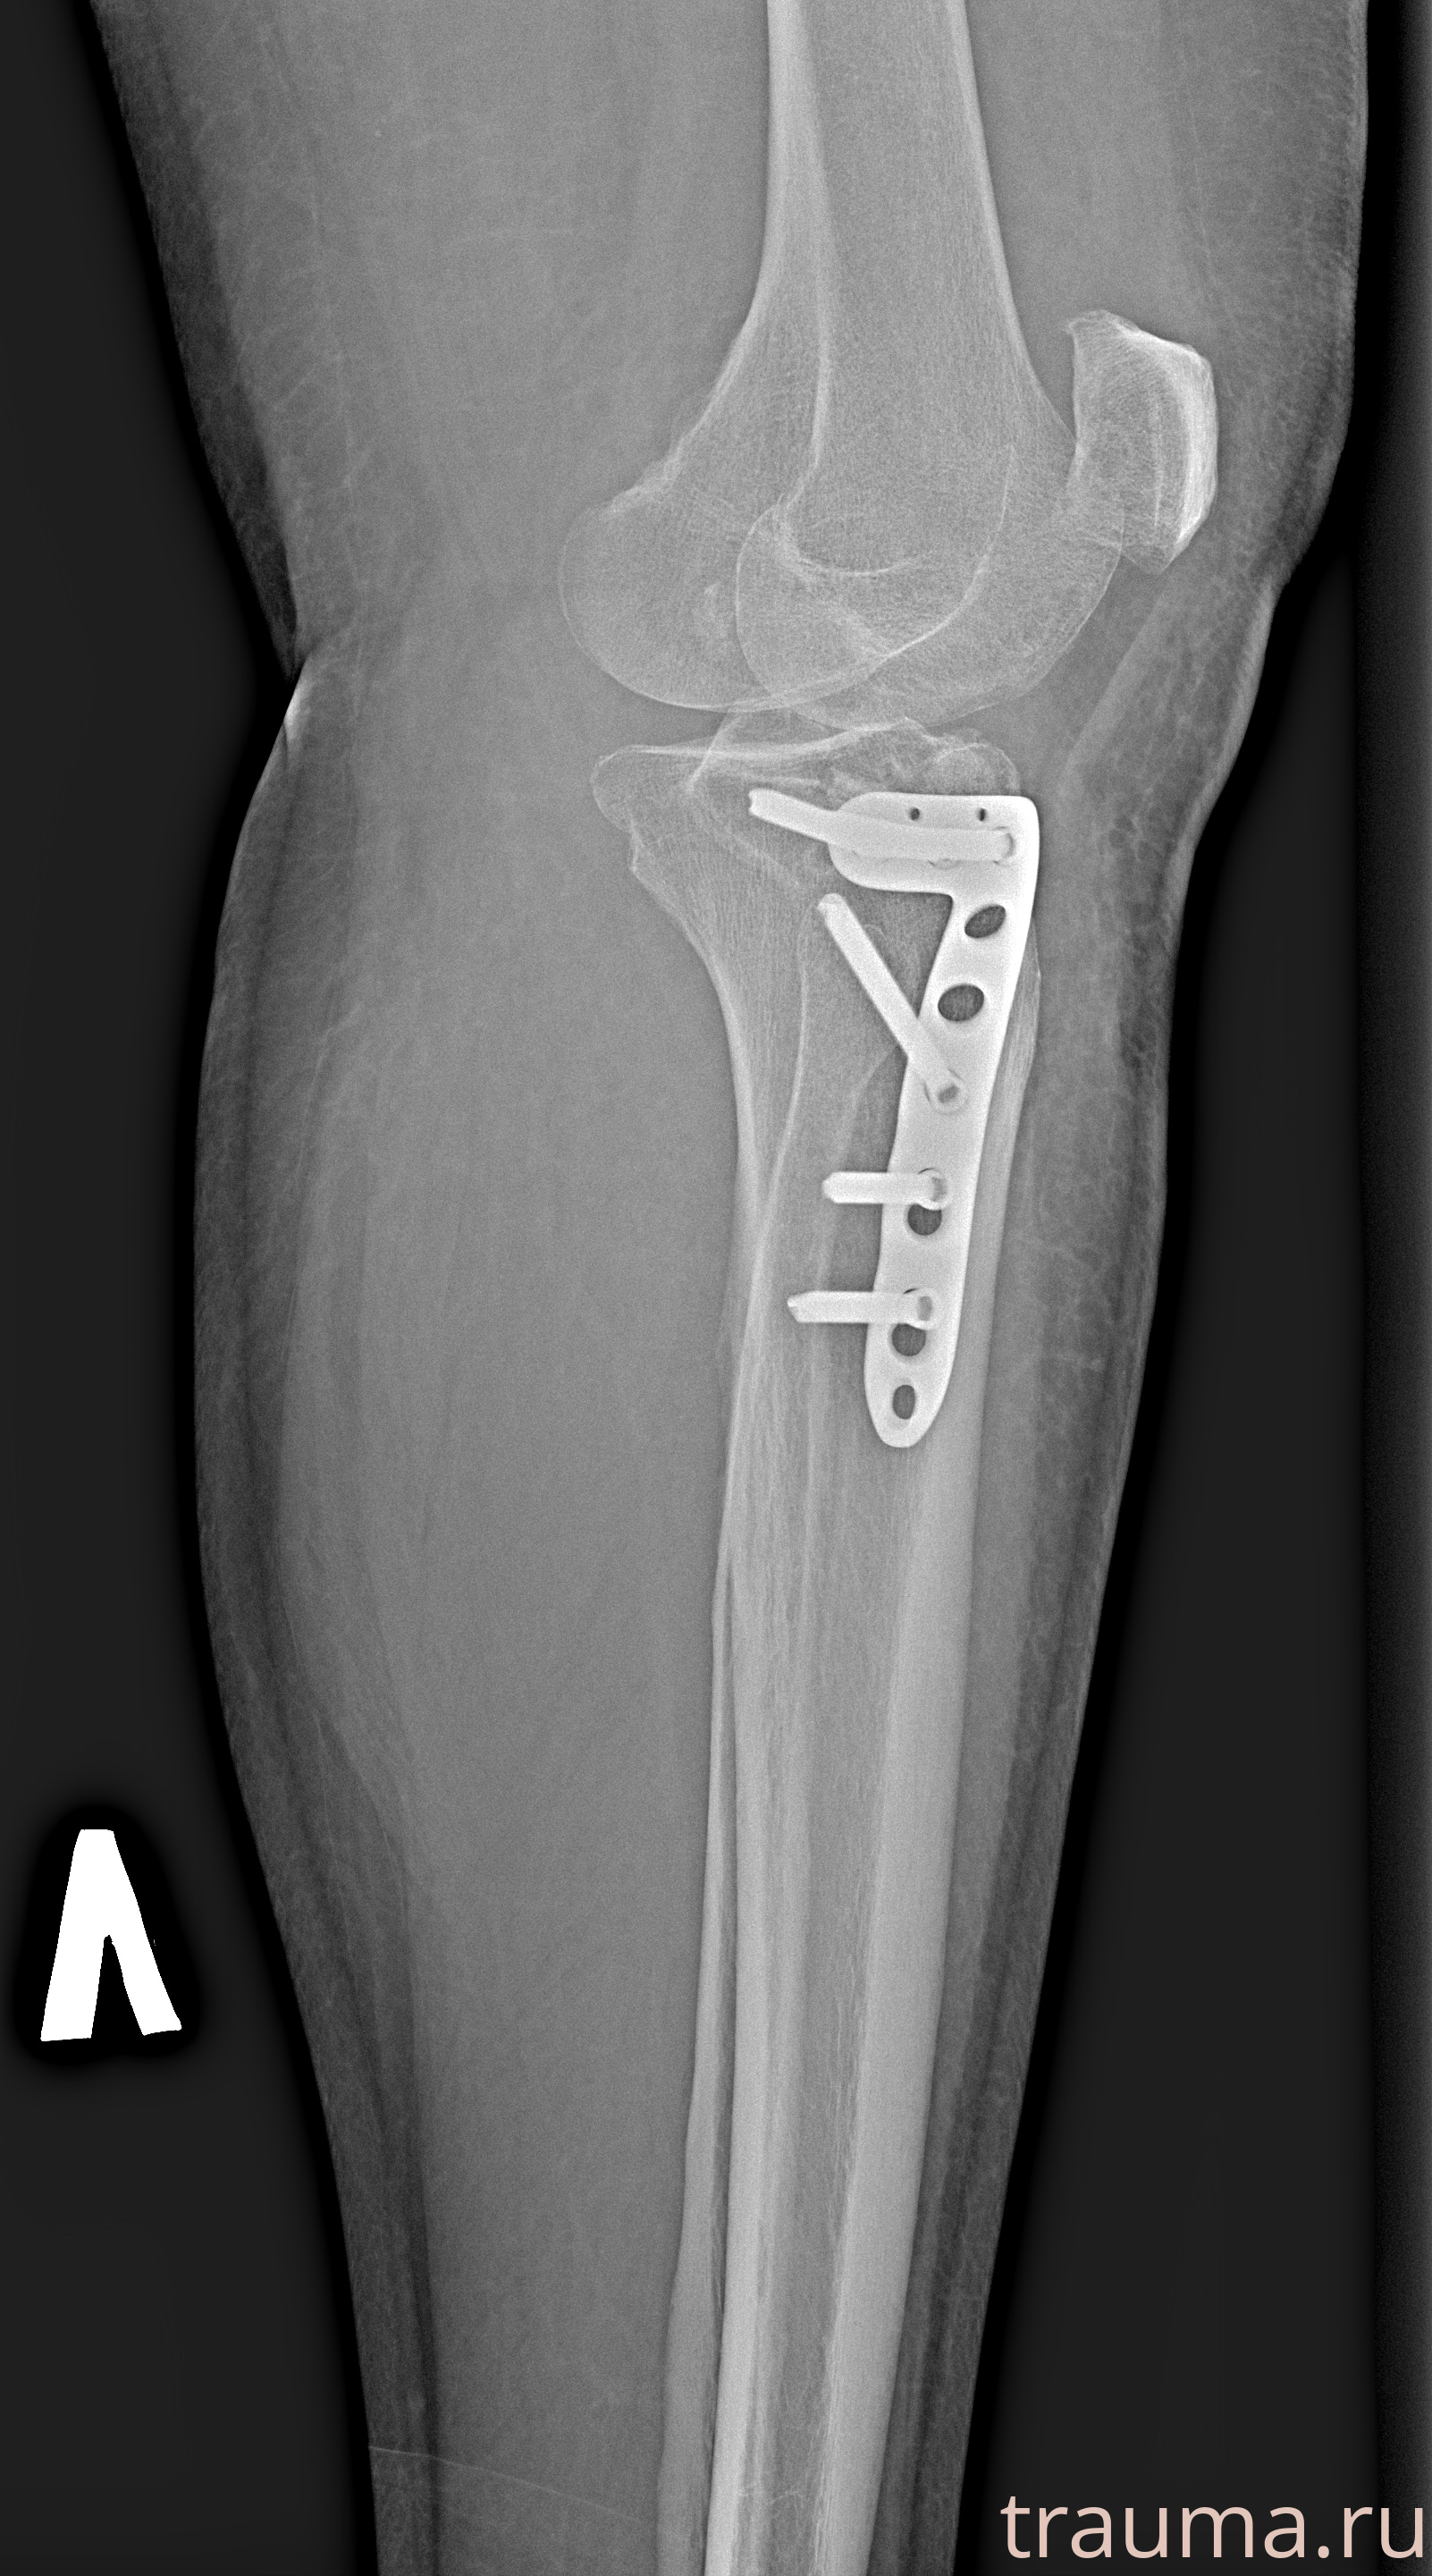

Рентгенограммы

Рентген на дому: по вашему адресу приезжает врач-рентгенолог, травматолог-ортопед с мобильным рентгеновским аппаратом, проводит диагностику травмы или заболевания, делает необходимые рентгенограммы, дает рекомендации по дальнейшему лечению. Получить качественные снимки в домашних условиях возможно благодаря уникальной методике, разработанной МосРентген Центром для института  Склифосовского